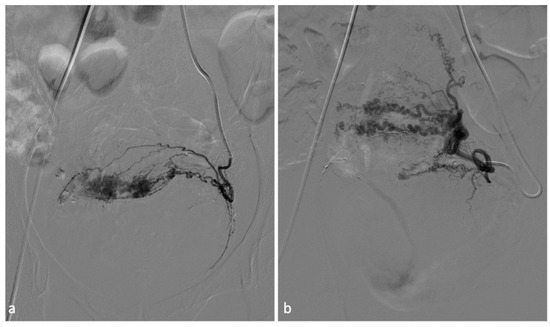

Figure 4.

Uterine artery embolization for leiomyoma. A 27-year-old patient presenting with menometrorrhagias and pelvic pain. TVUS and MRI demonstrated a voluminous isthmic uterine leiomyoma (12 cm of diameter). Selective left uterine artery arteriogram (a) shows multiple vessels feeding the large leiomyoma. Embolization through the release of embolizing microparticles was performed. Post-embolization left artery arteriogram (b) shows good devascularization of the leiomyoma. Post-embolization selective right uterine arteriogram (c) showed ectasia of the right tubal artery with origin of tubo-ovarian trunk for the ipsilateral annexal branches. Given the high risk of non-target embolization, embolization of the right uterine artery was not performed.